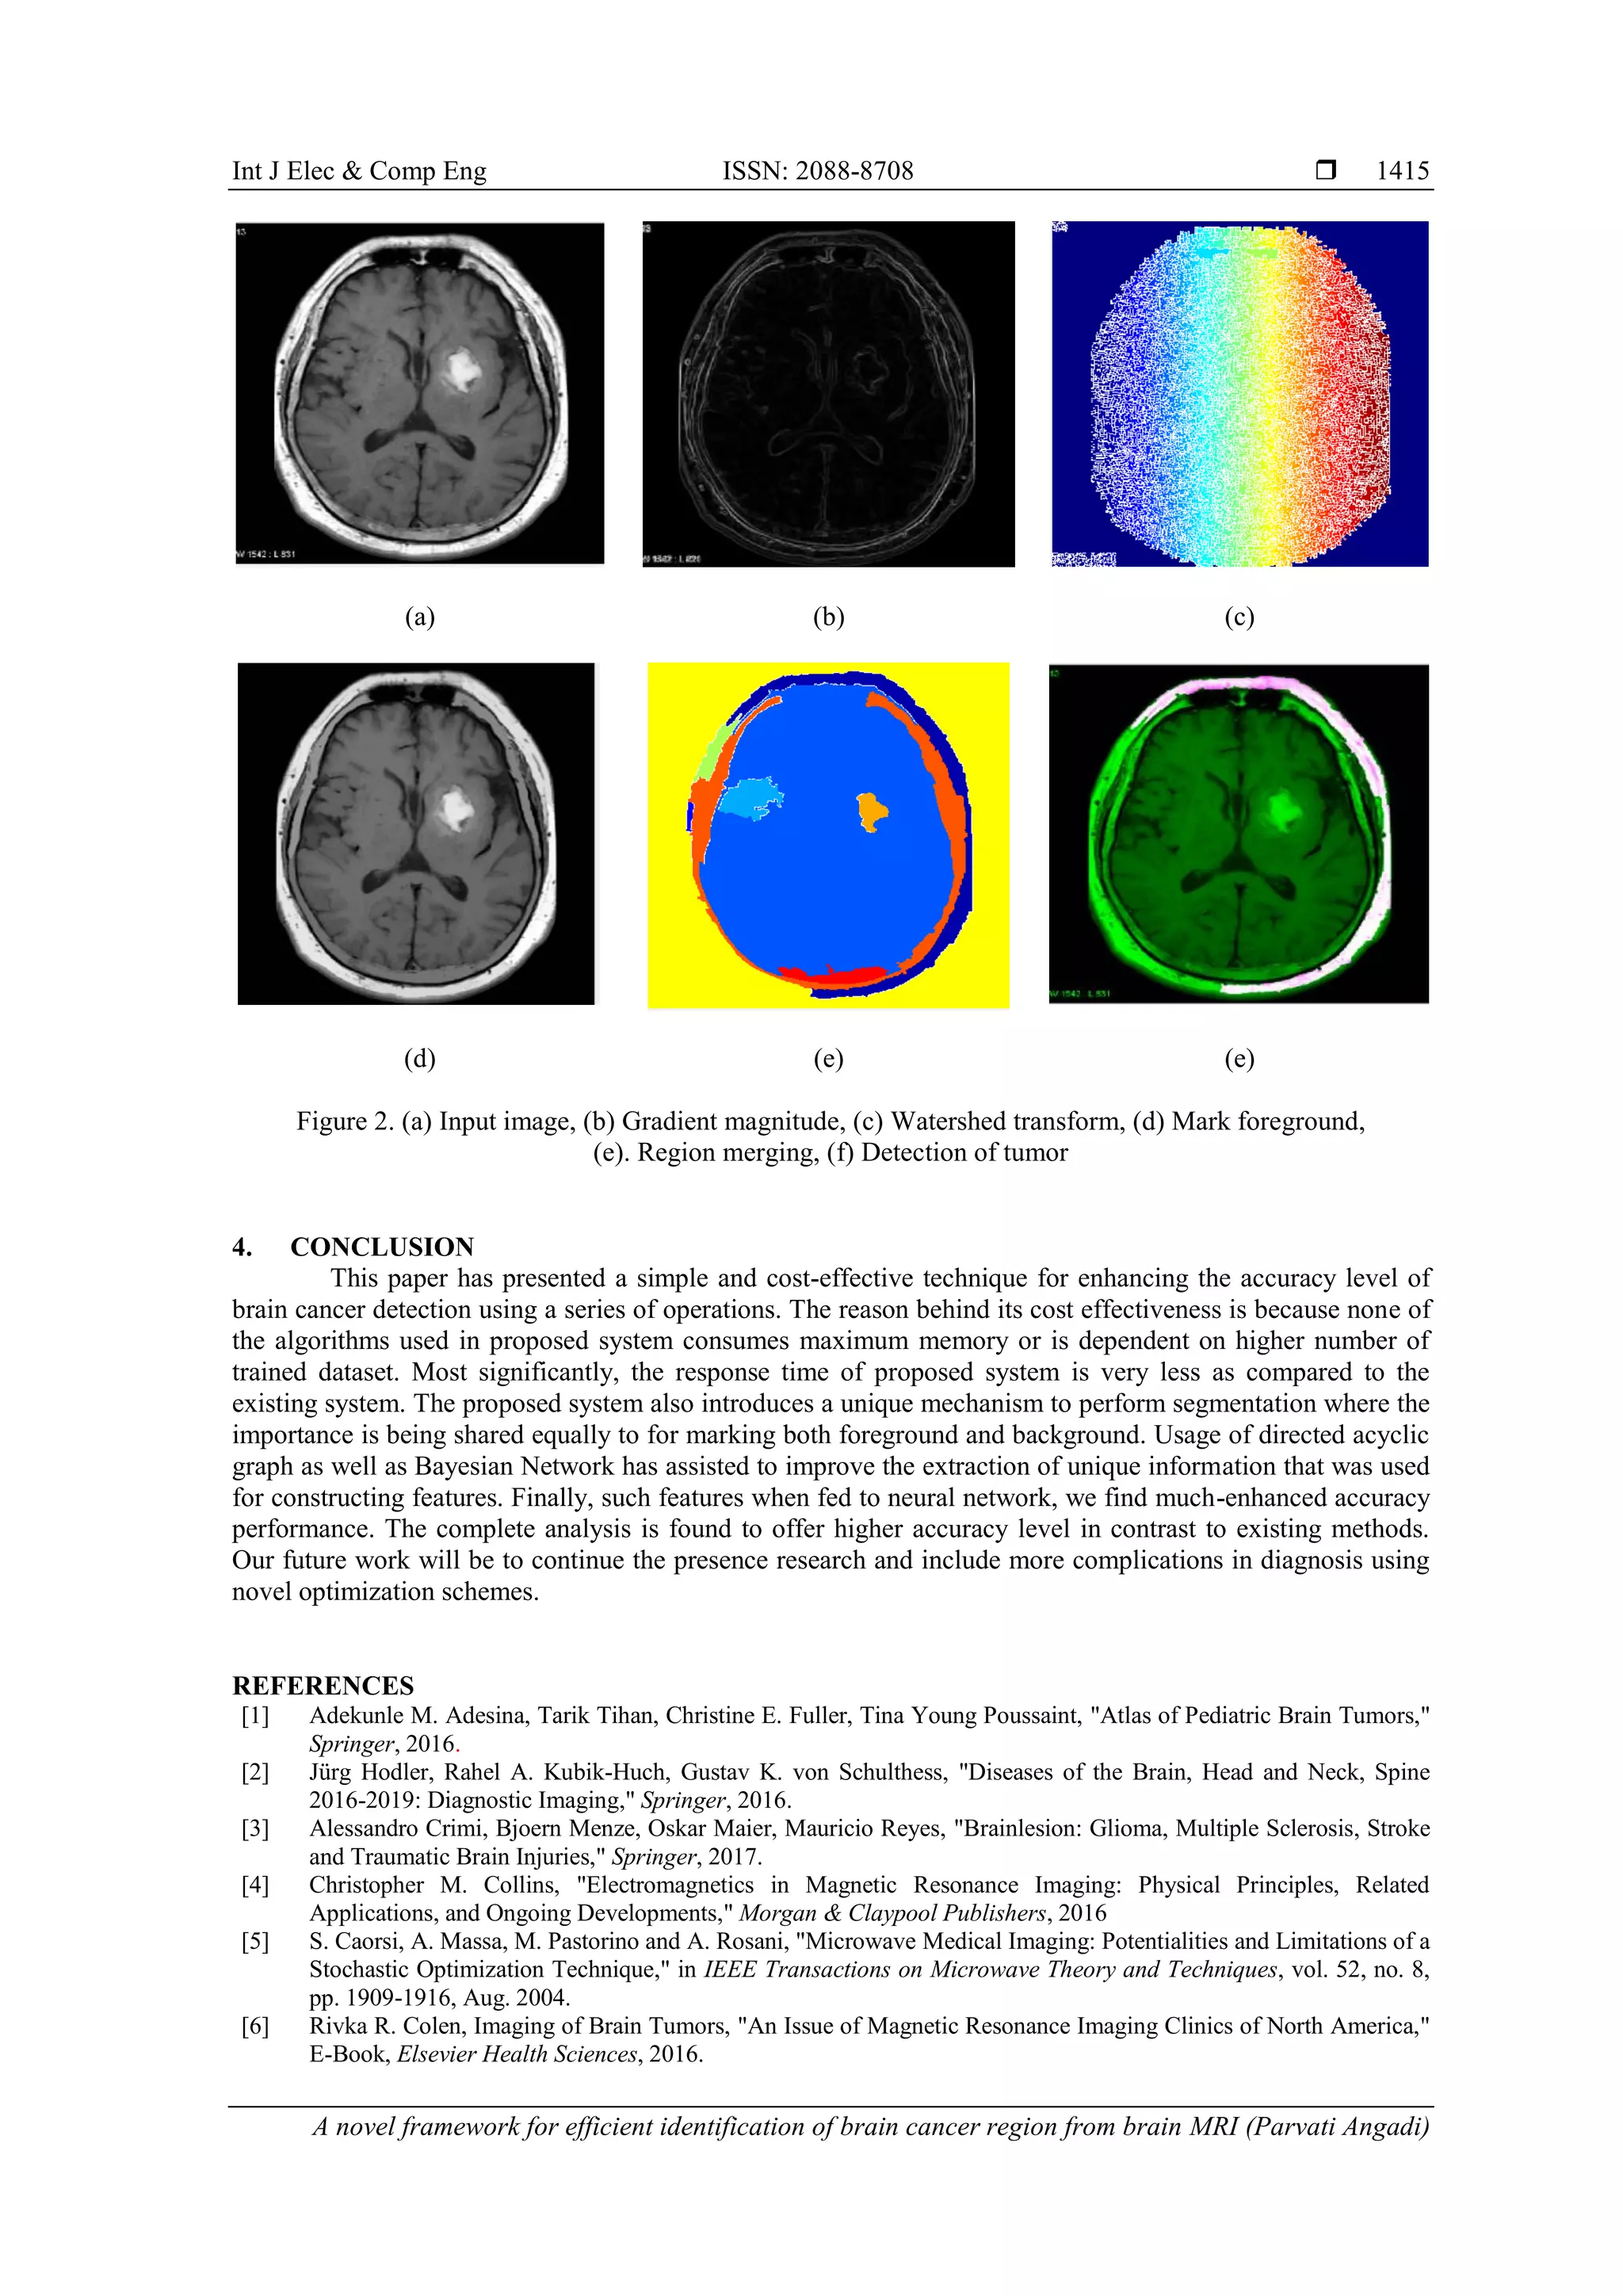

3. RESULTS ANALYSIS

This section discusses the result being obtained after implementing the concept written in the prior

section. The complete analysis is carried out on images obtained from MR-TIP database [31] where the

dimension of the images are approximately 618x630 with the occupation of 36.2 KB of memory. The visual

outcomes of the proposed system are shown in Figure 2 where it can be seen that input images after

subjecting to gradient magnitude loses its contrast and highlights for edge-based information Figure 2(b).

Applying watershed algorithm further assists in an effective segmentation process Figure 2(c) and hence it

highlights all the possible colors for the transformed image. In the process of segment, it was found that

foreground marking Figure 2(d) offers internal changes and not much on superficial changes followed by

region merging Figure 2(e). A closer look into the region merging operation in Figure 2(e) shows that the

suspected portion of cancer could be located within the region. Therefore, it can be said that true outcome

starts coming only after region merging operation. Further implying the direct acyclic graph and Bayesian

network, the identification performance of the cancerous regions has tremendously increased as well as it

offers better inference of the outcome of the processed image. At the same time, all the missing pixel

elements are successfully handled as all the encoding is carried out using Bayesian network. Even from the

accuracy viewpoint, the proposed system offers highly enhanced accuracy level as it can mitigate the

problem of overfitting to maximize the outcome of identification. Finally, applying neural network training

has further optimized the outcome the accuracy level of the proposed system with the shortest iteration of the

learning process. The complete optimization was carried out using damped least square algorithm.

(a) (b) (c)

(d) (e) (e)

Figure 2. (a) Input image, (b) Gradient magnitude, (c) Watershed transform, (d) Mark foreground,

(e). Region merging, (f) Detection of tumor